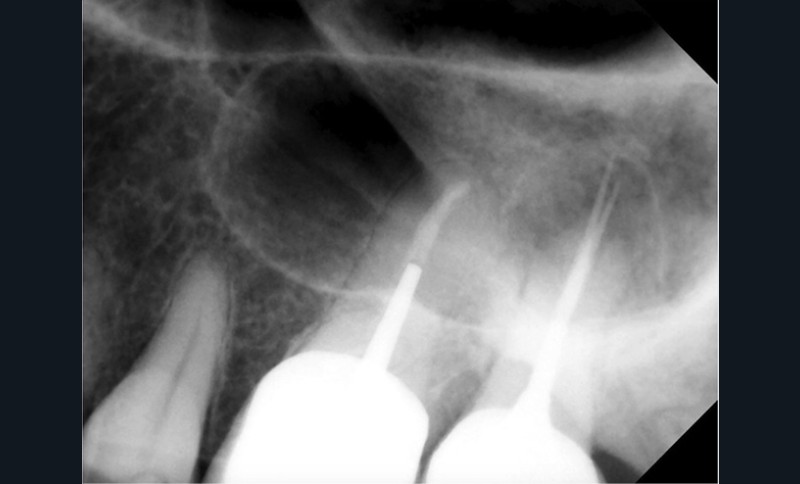

Si les isthmes sont particulièrement mis en évidence au niveau des molaires mandibulaires, cela devient médicalement important au niveau des molaires maxillaires.

La diffusion bactérienne et de leurs toxines, au niveau des molaires maxillaires est à l’origine d’un grand nombre de sinusites maxillaires chroniques, d’origine dentaire. Celles-ci sont principalement causées par l’absence de traitement du deuxième canal MV, qui existe dans 90 % des cas, et il est à noter que ces deux canaux – MV1 et MV2 – sont également reliés par un isthme.

Le nettoyage des isthmes intercanalaires reste un réel problème, et semble responsable de nombreux échecs [43]. Par ailleurs, il est nécessaire d’utiliser des instruments qui évitent de propulser les débris, tant apicalement que latéralement, en obturant les entrées isthmiques avec des débris compactés.

L’utilisation d’instruments en nickel titane, tels que le XP Shaper (FKG), le Vortex blue (Dentsply) ou le Profile (Dentsply), optimise la remontée des débris et s’inscrit dans cette nouvelle philosophie. En conséquence, la combinaison XP Shaper, XP Finisher et l’irrigation avec l’Er:YAG semblent optimiser nos traitements [44,45].

Le passage du laser est répété plusieurs fois, en début, au milieu et en fin de préparation. Un protocole peut alors être proposé : 40 mJ ; 20 Hz (fig. 7). L’utilisation de biocéramiques Bioroot (Septodont) ou Total Fill R (FKG) permet de sceller le système ainsi nettoyé, en assurant une action biologique de longue durée [46] (fig. 8a à c).